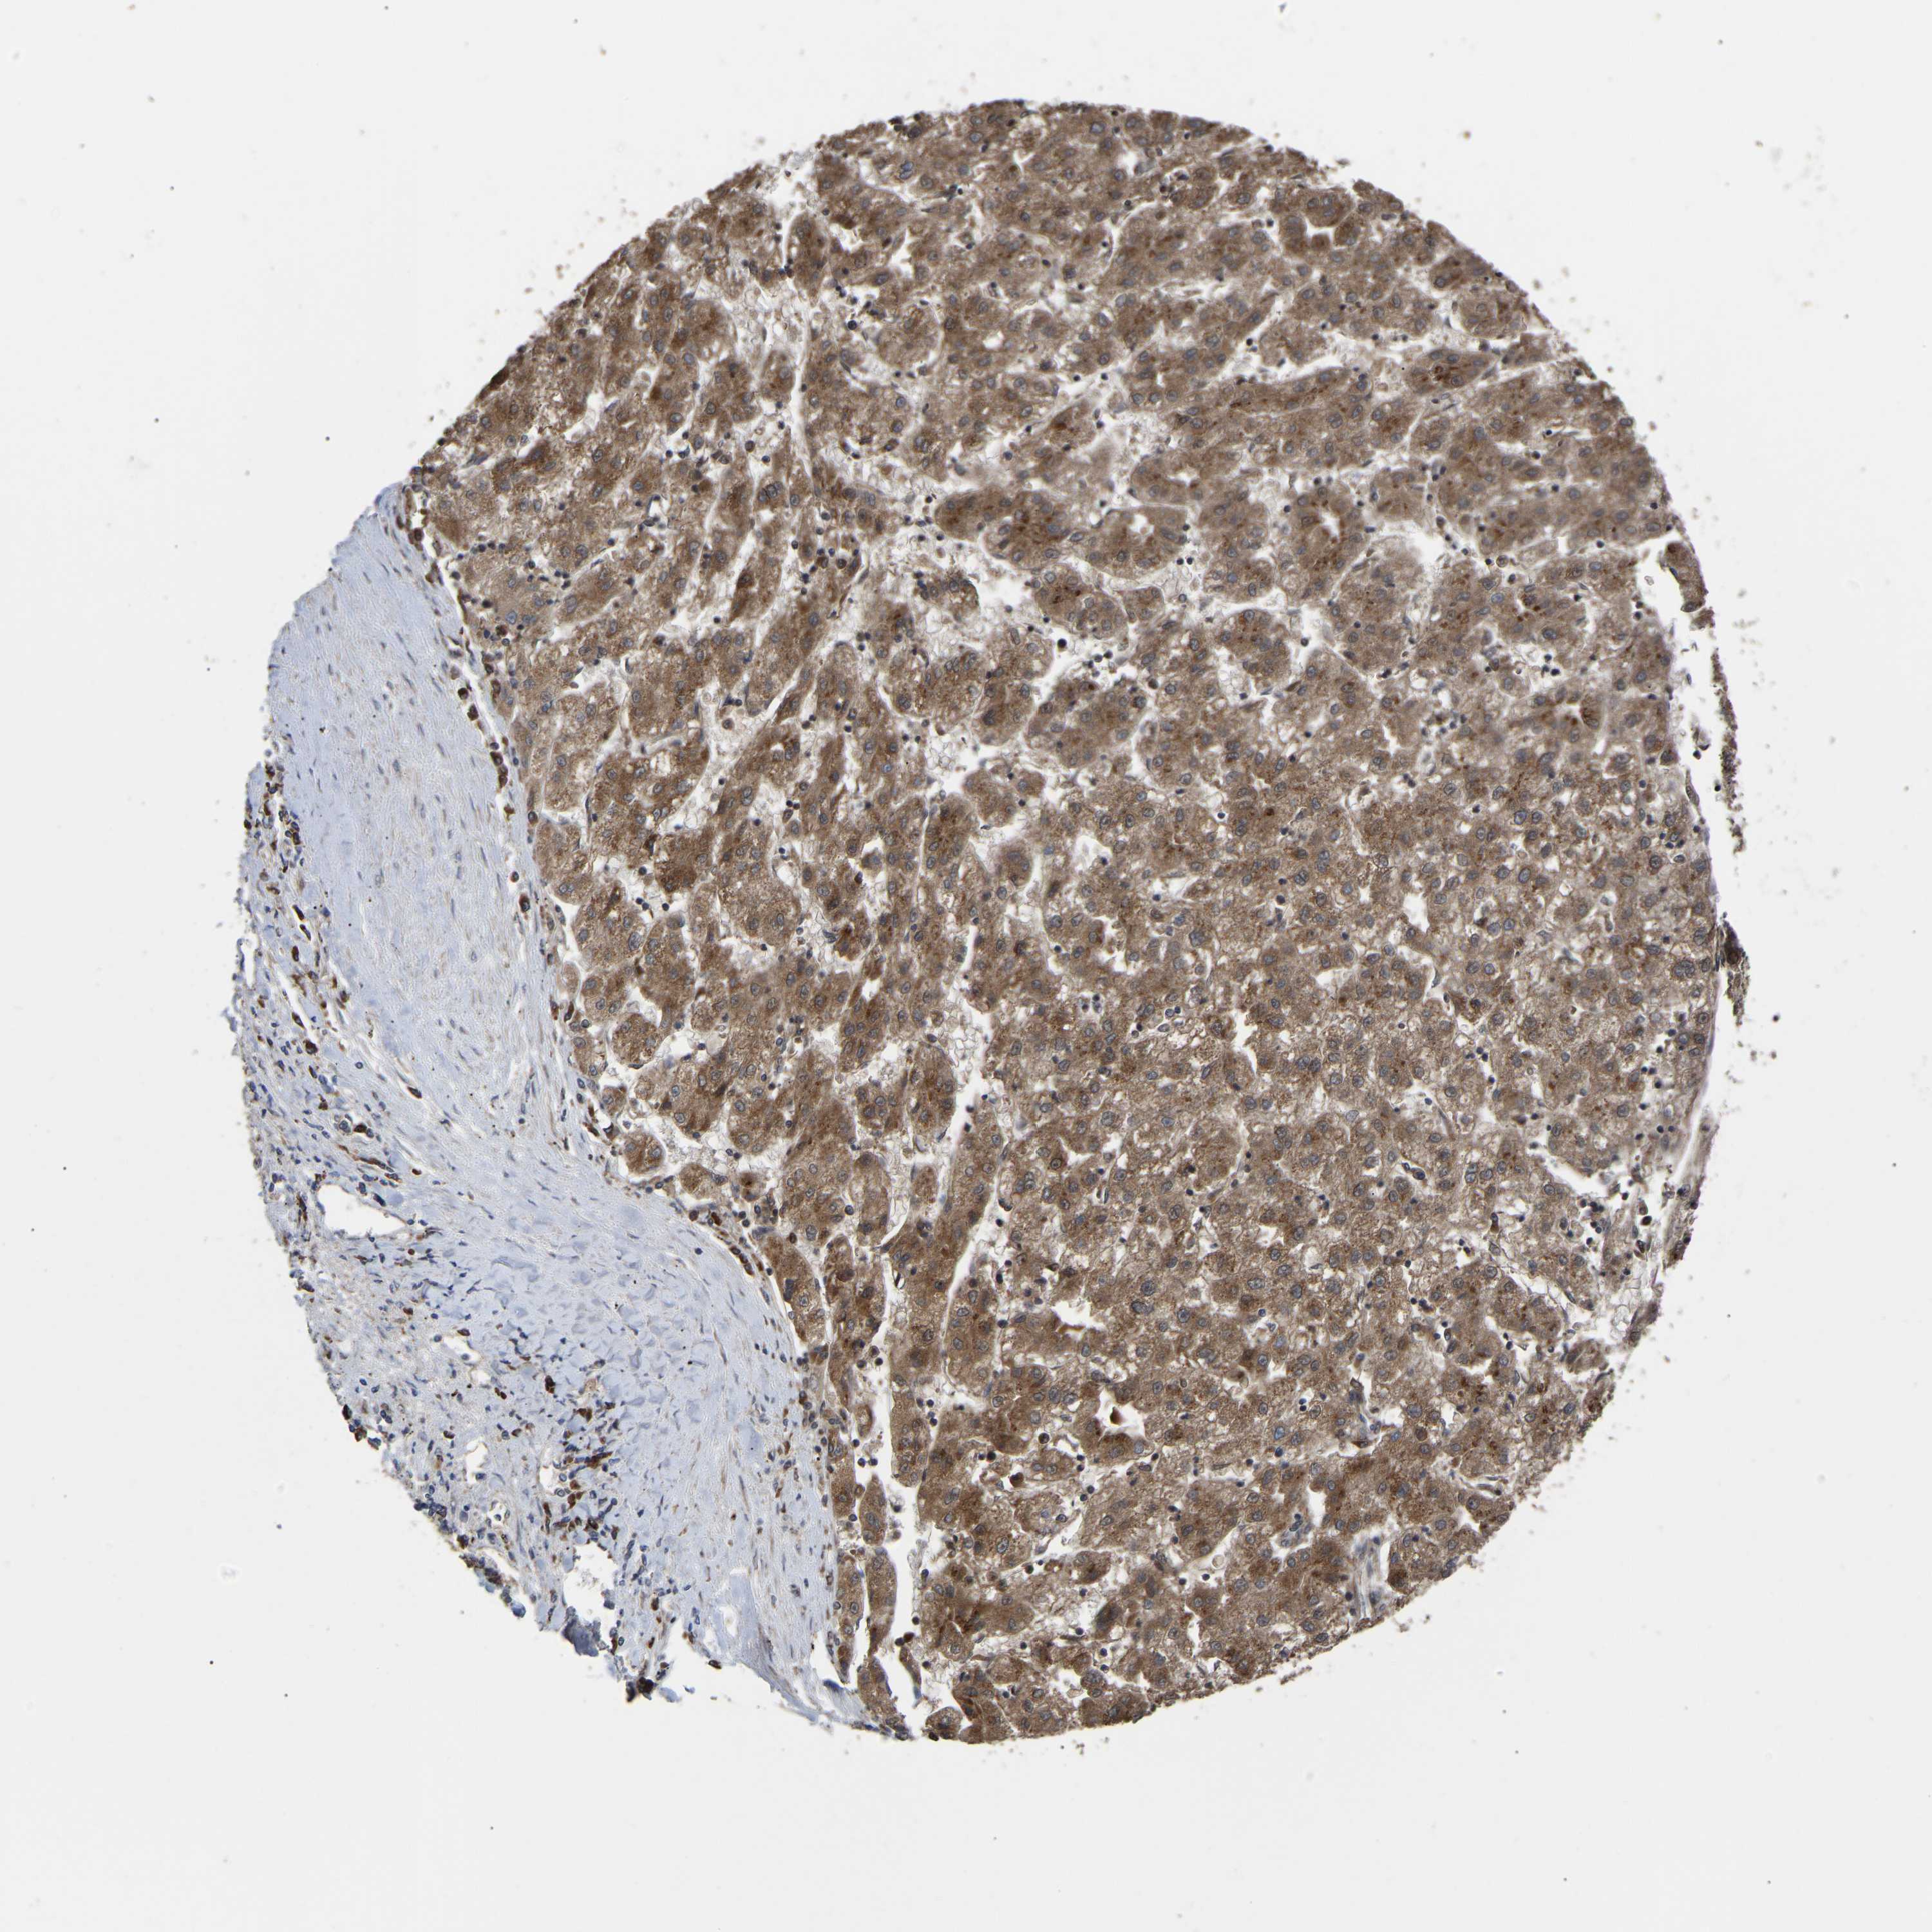

LIVER CANCER - Protein expressioni

A mouse-over function shows sample information and annotation data. Click on an image to view it in a full screen mode. Samples can be filtered based on level of antibody staining by selecting one or several of the following categories: high, medium, low and not detected. The assay and annotation is described here.

Note that samples used for immunohistochemistry by the Human Protein Atlas do not correspond to samples in the TCGA dataset.

Antibody stainingi

Antibody staining in the annotated cell types in the current human tissue is reported as not detected, low, medium, or high, based on conventional immunohistochemistry profiling in selected tissues. This score is based on the combination of the staining intensity and fraction of stained cells.

Each image is clickable and will lead to virtual microscopy that enables deeper exploration of all samples and also displays staining intensity scores, fraction scores and subcellular localization as well as patient and tissue information for each sample.

Antibody HPA019369

Antibody HPA021323

Staining

High

Medium

Low

Not detected

Intensity

Strong

Moderate

Weak

Negative

Quantity

>75%

75%-25%

<25%

None

Location

Nuclear

Cytoplasmic/membranous

Cytoplasmic/membranous,nuclear

Cholangiocarcinoma

Carcinoma, Hepatocellular, NOS